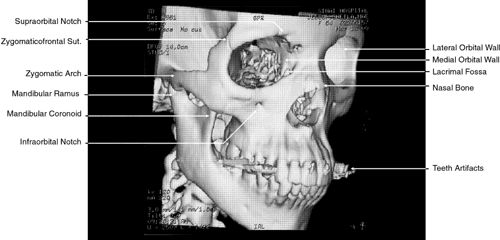

More recently, evolution in CT software has permitted the creation of high-resolution 3D images (Fig. 1).8 This has been of particular interest in cases of traumatic and congenital bony defects of the skull, where such images are quite useful in planning reconstructive efforts. With additional mathematical manipulation of the attenuation coefficients obtained from cross-sectional 2D slices, 3D images can be reconstructed. This is accomplished by estimating the interstice voxel HU values. These are generally assumed to be a weighted average of the HU values for the voxels of the two adjacent slices. The locations of the voxels are then described in terms of a 3D coordinate system with the z-axis parallel to the CT scanner table, the y-axis perpendicular to the top of the table, and the x-axis parallel to the CT scanner gantry opening. These images can then be reconstructed in either gray-scale or false color and recorded on film or tape.

Fig. 1. Three-dimensional computed tomography reconstruction of facial bones and orbit.

The globe is shown in Figure 12. The orbit and periorbital structures are shown in Figures 13 through 16, and the optic canal is shown in Figures 17 through 26. The cavernous sinus and optic chiasm are shown in Figures 27 and 28, and the posterior visual pathway and cranial nerves are shown in Figures 29 through 33.

Fig. 13. Three-dimensional reconstruction of orbit and infraorbital structures (Water's view).

Fig. 14. Three-dimensional reconstruction of orbit (anterior view).

Fig. 15. Three-dimensional reconstruction of orbit and cranial cavity (superior view).

Fig. 16. Three-dimensional bone reconstruction of cranial cavity structures (view from posterior cranial fossa).